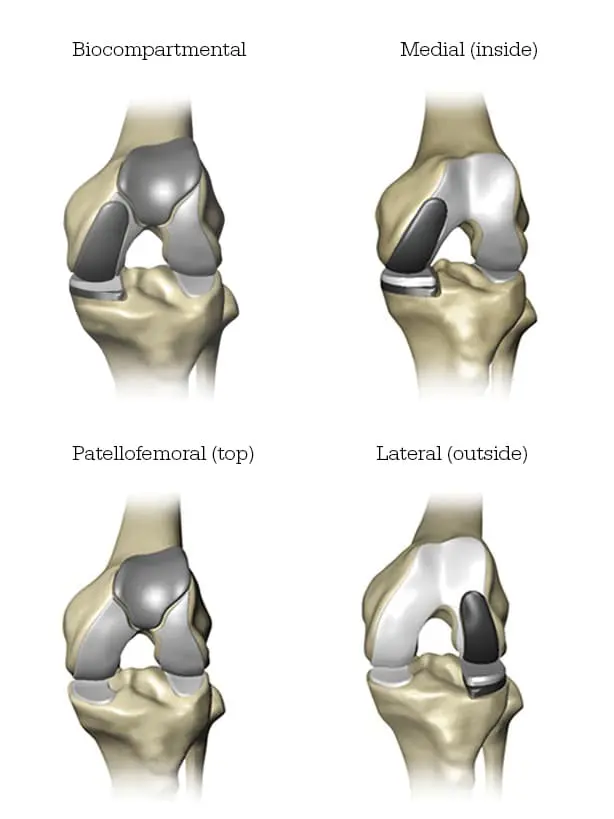

Mako Partial Knee replacement serves as a viable option for adults grappling with early to mid-stage osteoarthritis (OA) that hasn’t affected all three compartments of the knee. Depending on the location of arthritis within the knee, patients may receive an implant in various regions.